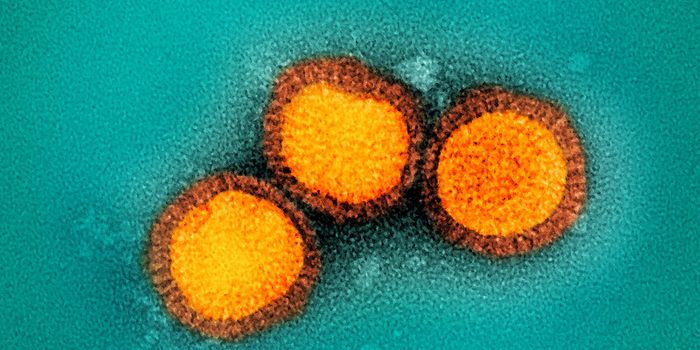

DEC 07, 2021Clinical & Molecular DXMore mutations, more transmissible, and more likely to infect vaccinated people—coronavirus variants such as Omicr ...